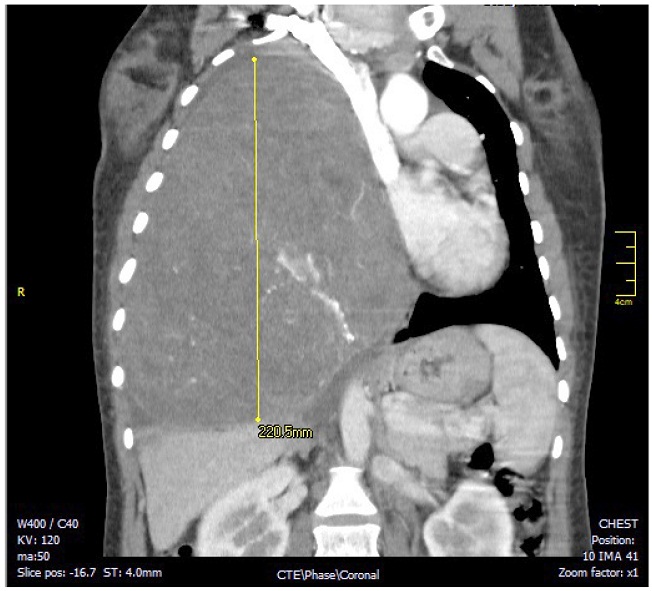

La radiografía de tórax inicial evidenció una opacidad que ocupaba el 70 % del hemitórax derecho, la tac contrastada de tórax evidenció una gran masa sólida de contornos lobulados que comprometía el 70 % del hemitórax derecho de origen extrapulmonar, heterogénea y con densidad de tejidos blandos, que desplazaba el mediastino y comprimía el corazón (figuras 1 y 2). Las dimensiones de la masa eran 16 x 18 x 22cm. Los diagnósticos planteados por el radiólogo fueron teratoma, tumor fibroso pleural o secuestro pulmonar. La histopatología de la muestra, obtenida por biopsia percutánea con aguja cortante de la lesión, reportó un tumor fusocelular de aspecto benigno que pudiera tratarse de un tumor fibroso de la pleura; posteriormente, la inmunohistoquímica confirmó el diagnóstico por inmunoreactividad de las células tumorales para bcl2, cd34, cd99 y stat6 compatible con un tumor fibroso solitario.

Nota: evidencia el tfsp gigante que desplaza el mediastino y comprime la aurícula derecha.